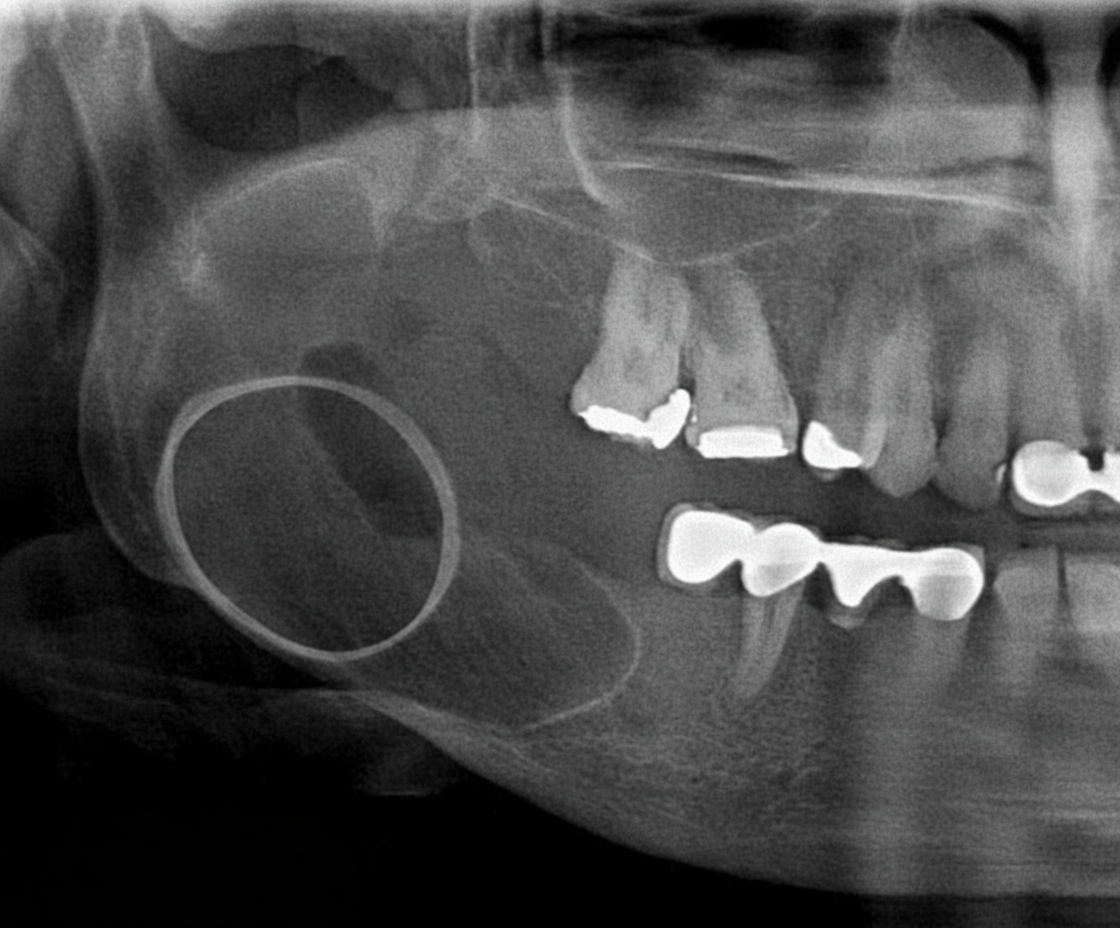

A radiograph of a 32-year-old patient reveals an asymptomatic lesion that was an accidental finding. What is the most likely diagnosis?

Explanation: ***Stafne bone cavity*** - Characteristically an **asymptomatic incidental radiographic finding** below the **inferior alveolar canal** in the posterior mandible, typically between the premolars and angle. - Represents a **developmental depression** in the lingual cortex filled with salivary gland tissue, appearing as a well-defined radiolucency with **sclerotic borders**. *Radicular cyst* - Associated with **non-vital teeth** and typically presents with symptoms like pain, swelling, or **periapical pathology**. - Located at the **apex of a tooth** rather than below the inferior alveolar canal, and usually has a history of dental trauma or caries. *Dentigerous cyst* - Surrounds the **crown of an unerupted tooth**, most commonly **impacted third molars** or canines. - Presents as a **pericoronal radiolucency** and may cause **displacement** of the associated tooth, not as an isolated mandibular depression. *Lateral periodontal cyst* - Occurs along the **lateral root surface** of vital teeth, typically in the **anterior mandible** or premolar region. - Often presents with **localized gingival swelling** and is associated with vital teeth, unlike the asymptomatic nature described.